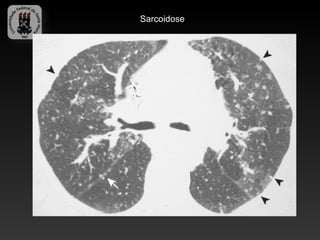

-SARCOIDOSE

-Doença idiopática caracterizada por granulomas não caseosos.

-Envolvimento pulmonar bilateral é o habitual e a linfadenopatia é a manifestação

intratorácica mais comum.

-Cerca de 10% tem radiografia de torax normal.

-Infecção sobreposta é responsável por uma significativa morbidade e mortalidade.

-Achados da TC:

-   Linfadenopatia (75-80%), calcificações em casca de ovo

-   Áreas de atenuação em vidro fosco

-   Nódulos subpleurais e perivascular

-   Espessamento irregular peribroncovascular e dos septos interlobulares

-   Predomínio nas regiões médias e superiores

-   Fibrose – complicação tardia